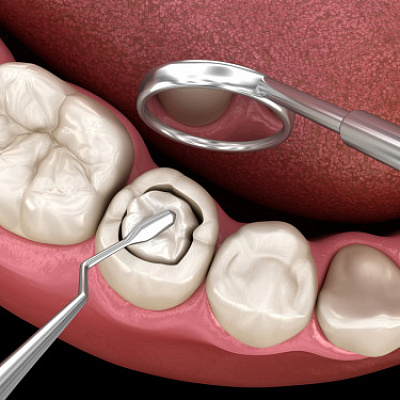

Консервативное или эндодонтическое лечение периодонтита проводится при относительно нормальном состоянии зуба и периодонта. Обычно при остром течении патологического процесса, когда изменений в тканях еще нет. Или они не столь существенны. Терапия проводится в несколько стадий:

- высверливание тканей зуба, получение доступа к пульпарной камере, а также каналам;

- удаление нервно-сосудистого пучка, т.н. депульпирование зуба с применением специальных методов и инструментов;

- обработка корневых каналов, расширение, применением антибиотиков и антисептических препаратов;

- пломбирование каналов, чтобы обеспечить их герметичность и не допустить повторного развития инфекции, современная эндодонтия предполагает использование микроскопа и специальных инструментов, чтобы не пропустить ни миллиметра;

- реставрация зуба — восстановление коронковой части.